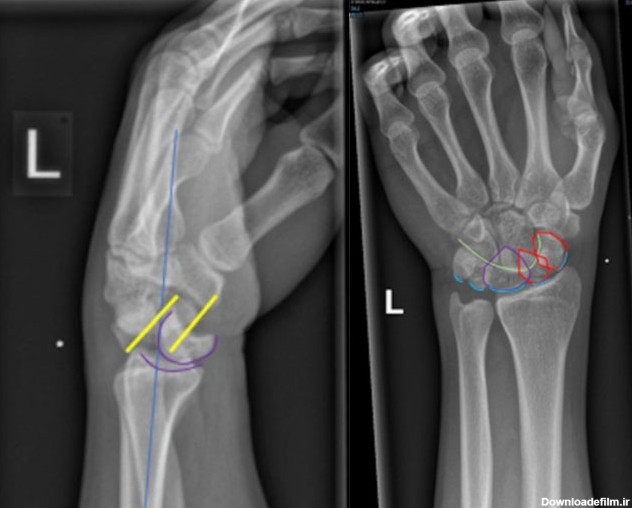

شکستگی صفحه رشد مچ دست شکستگی صفحه رشد مچ دست : در این مقاله به بحث پیرامون نوعی از شکستگی های مچ می پردازیم که در کودکان روی می دهد...

شکستگی های استخوانهای مچ دست شایع در اندام فوقانی به حساب می آید که در اثر زمین خوردن و هایپراکستنشن مچ دست بیش از 95 درجه و تحت فشار قرار گرفتن اسکافویید.

صفحه رشد چه کاری انجام می دهد؟ - علائم بسته شدن صفحه رشد - علائم صفحه رشد بسته - افزایش قد بعد از بسته شدن صفحات رشد چجوری ممکن است؟ + عکس صفحه رشد باز و بسته